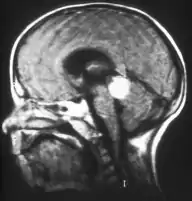

Inherited forms of retinoblastomas are more likely to be bilateral. In addition, inherited uni- or bilateral retinoblastomas may be associated with pineoblastoma and other malignant midline supratentorial primitive neuroectodermal tumors (PNETs) with a dismal outcome; retinoblastoma concurrent with a PNET is known as trilateral retinoblastoma.[15] A 2014 meta-analysis showed that 5-year survival of trilateral retinoblastoma increased from 6% before 1995 to 57% by 2014, attributed to early detection and improved chemotherapy.[16]

In about two-thirds of cases,[27] only one eye is affected (unilateral retinoblastoma); in the other third, tumors develop in both eyes (bilateral retinoblastoma). The number and size of tumors on each eye may vary. In certain cases, the pineal gland or the suprasellar or parasellar region (or in very rare cases other midline intracranial locations) is also affected (trilateral retinoblastoma). The position, size, and quantity of tumors are considered when choosing the type of treatment for the disease.

If the eye examination is abnormal, further testing may include imaging studies, such as computerized tomography (CT), magnetic resonance imaging (MRI), and ultrasound.[28] CT and MRI can help define the structure abnormalities and reveal any calcium depositions. Ultrasound can help define the height and thickness of the tumor. Bone marrow examination or lumbar puncture may also be done to determine any metastases to bones or the brain.

Drawing of a large retinoblastoma Aspect of trilateral retinoblastoma on MRI

Traditional ultrasound B scan can detect calcifications in the tumour while high-frequency ultrasound B scan is able to provide higher resolution than the traditional ultrasound and determine the proximity of the tumour with front portion of the eye. MRI scan can detect high-risk features such as optic nerve invasion; choroidal invasion, scleral invasion, and intracranial invasion. CT scan is generally avoided because radiation can stimulate the formation of more eye tumours in those with RB1 genetic mutation.[35]